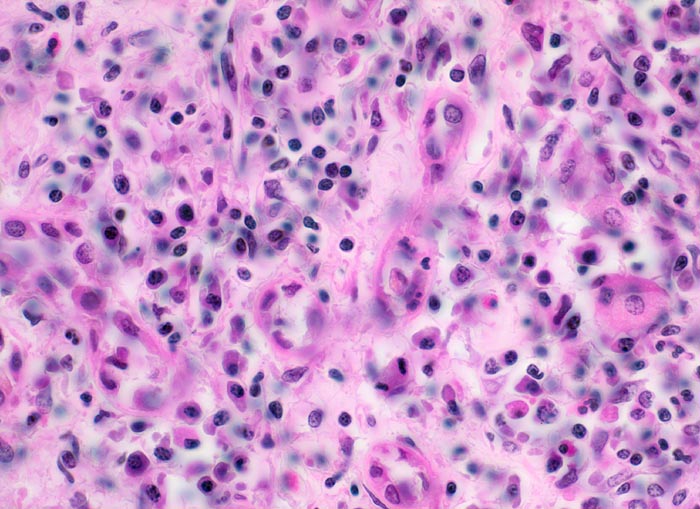

Aktive Vaskulitis: Infiltration und/oder Destruktion der Gefässwand durch ein Entzündungsinfiltrat. Intraluminale Fibrinthromben oder intramurale Fibrinablagerungen (fibrinoide Nekrose).

Befallen sind prärenale und grössere intrarenale Nierenarterienäste bei meist fehlender Beteiligung der Arteriolen und definitionsgemäss fehlendem Befall der glomerulären Kapillaren. Die betroffenen Gefässe zeigen segmentale transmurale oft durch Thrombosierung komplizierte Wandnekrosen mit initial granulozytenreichem Infiltrat. Im Verlauf werden die Nekrosen durch Granulations- und Narbengewebe organisiert. An grossen Arterien kann dies zu Knotenbildungen und Aneurysmata führen. Oft findet man in ein und demselben Gefäss frische Nekrosen neben reparativen Veränderungen und Narben. Das übrige Nierengewebe zeigt als Folge der Vaskulitis Kollapsglomerula, Infarkte und ischämische Tubulusatrophie mit begleitender interstitieller Fibrose und Entzündung.